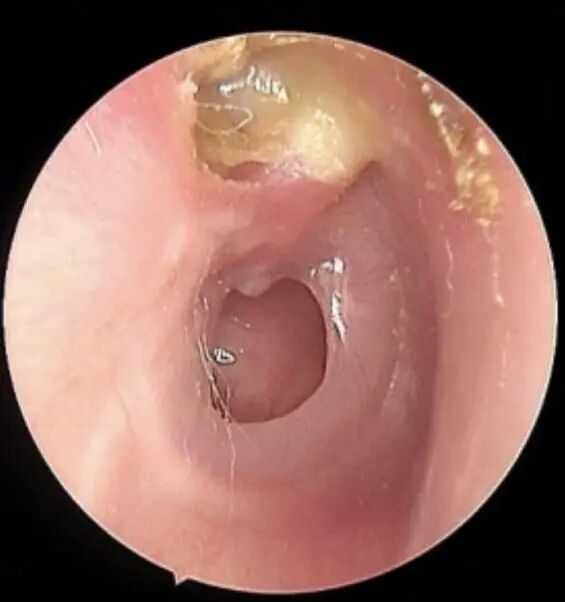

慢性化脓性中耳炎:就是这次“感冒”后,留下了后遗症——鼓膜破了个洞,一直长不好。这个穿孔就像一扇关不紧的门,让细菌和病毒可以随时进出,导致感染反复发作,持续流脓。通常流脓、穿孔的过程会持续超过3个月。

鼓膜穿孔

声音需要通过鼓膜和听小骨链振动才能传入内耳。鼓膜上的穿孔和听小骨被炎症侵蚀,会像一套生锈的传动装置,导致声音传导效率大大降低。